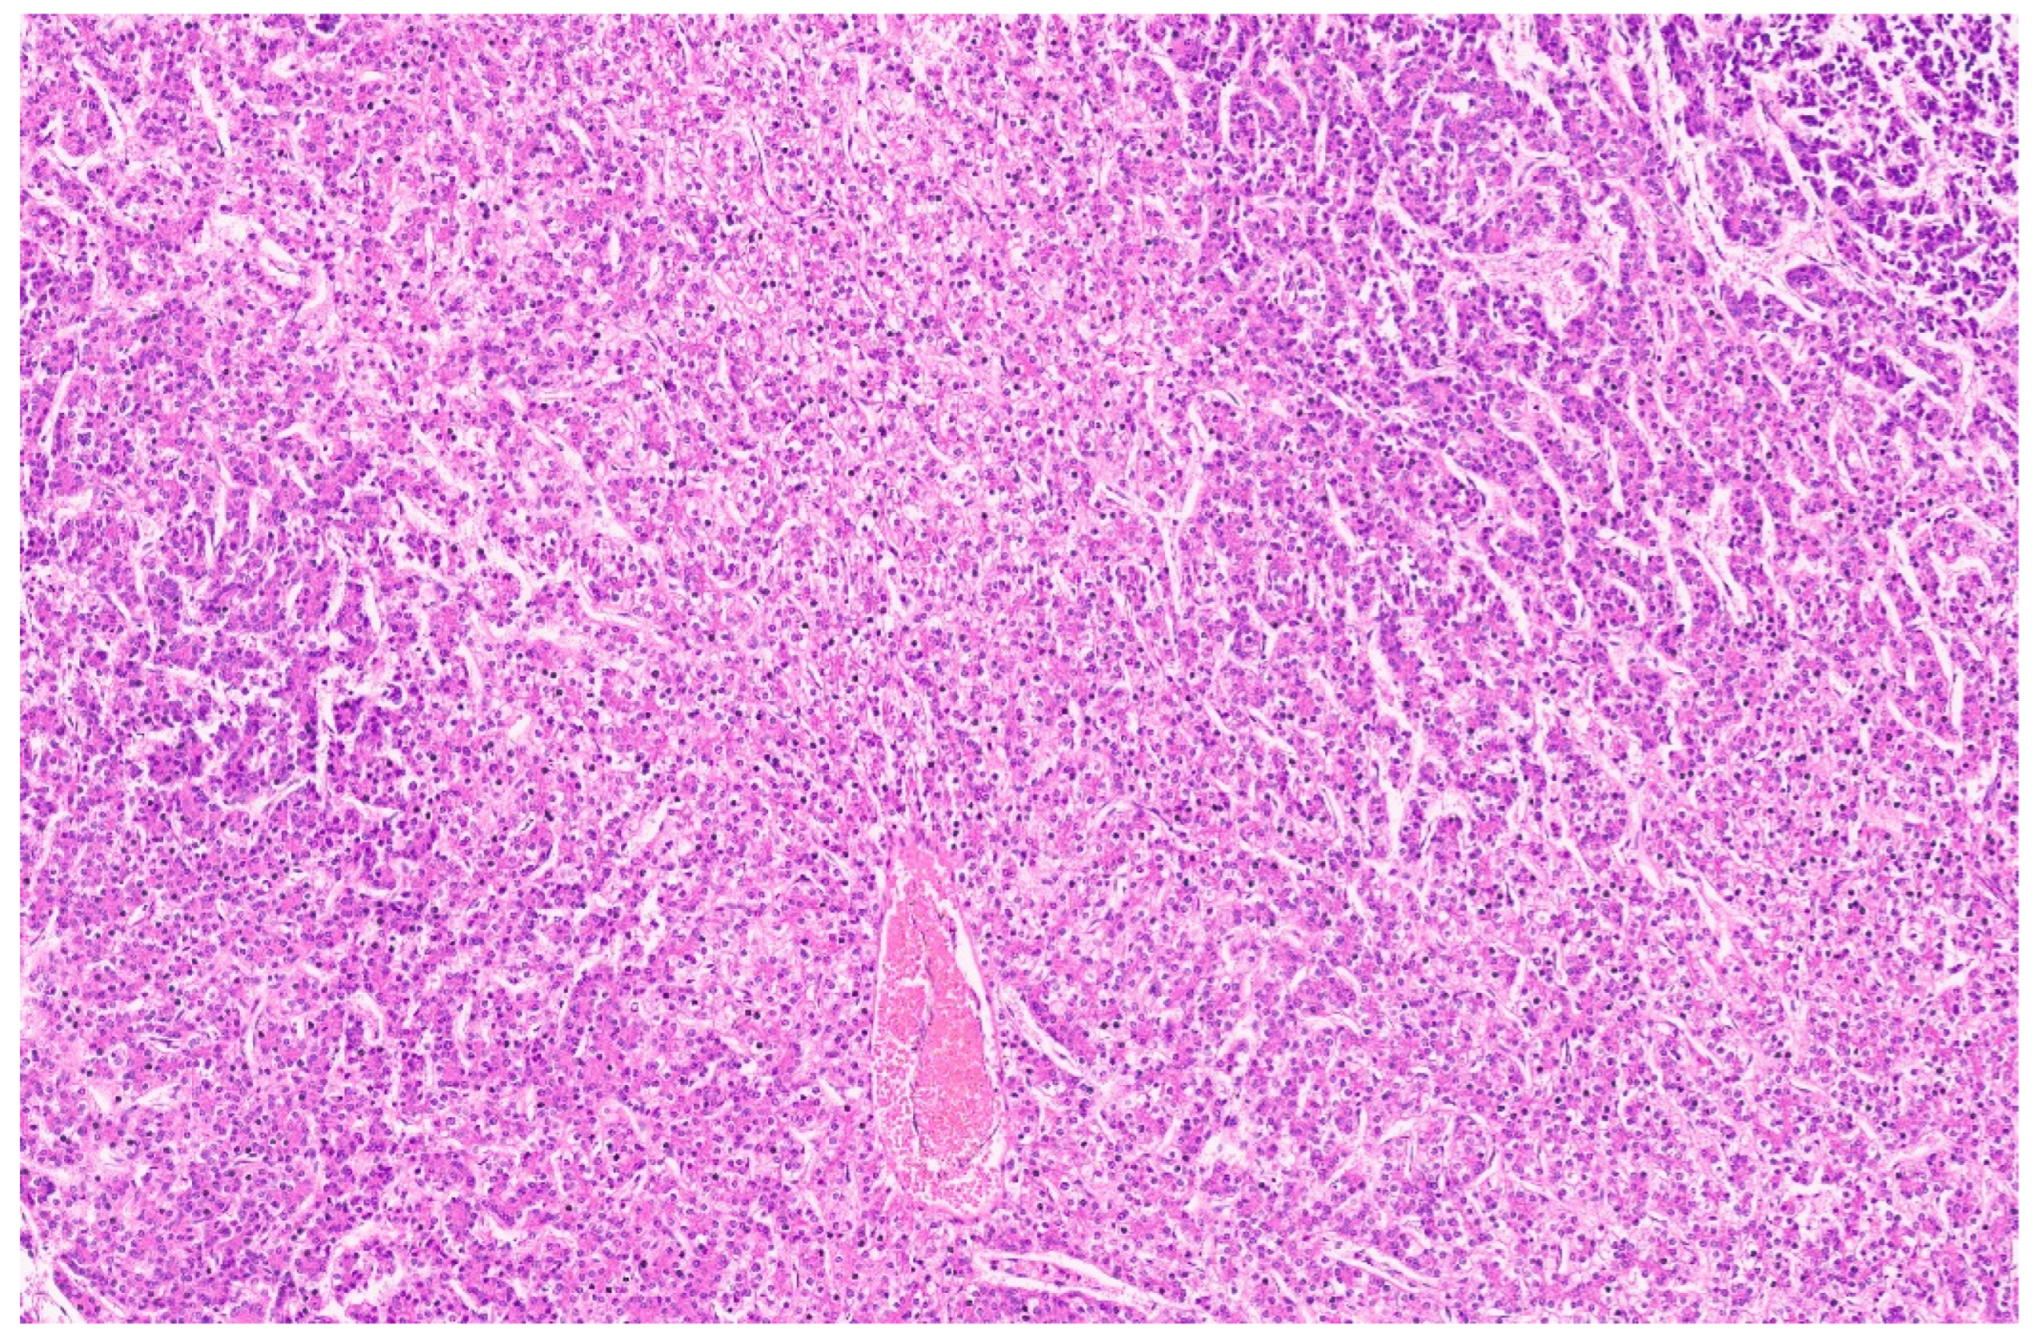

16.3. Pathology

| Histopathology | Well Differentiated | Moderately Differentiated | Poorly Differentiated |

|---|---|---|---|

| Arrangement | Trabeculae that are at least 3 cells thick and lined by sinusoids, pseudoacinar arrangement | Trabeculae that are 15–20 cells thick lined by sinusoids, pseudoacinar arrangement | Sheets or nests of cells not resembling hepatocytes. |

| Cells and nuclei | Resemble hepatocytes with mild nuclear pleomorphism, centrally placed round nuclei, and abundant cytoplasm | Moderate nuclear pleomorphism, large nuclei with prominent nucleoli and intranuclear inclusions, abundant cytoplasm. | High N/C ratio, nuclear pleomorphism, prominent nucleoli and intranuclear inclusions, numerous mitosis |

| Necrosis | Usually absent | May be seen | Present |

| Immunohistochemistry | Variable glypican 3 and glutamine synthetase levels. Negative for β-catenin nuclear staining | Glypican 3 and glutamine synthetase are positive in 50% of cases, β-catenin is variable | Glypican 3 and glutamine synthetase |